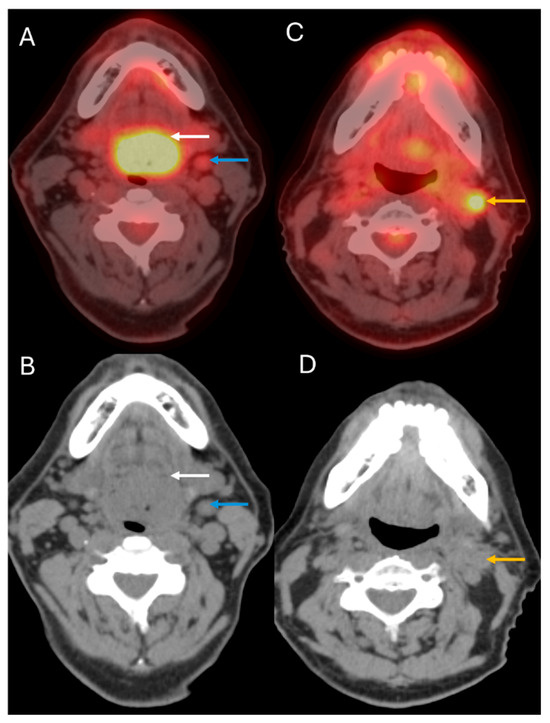

4. Staging of Cervical Nodal Metastases

1. Introduction